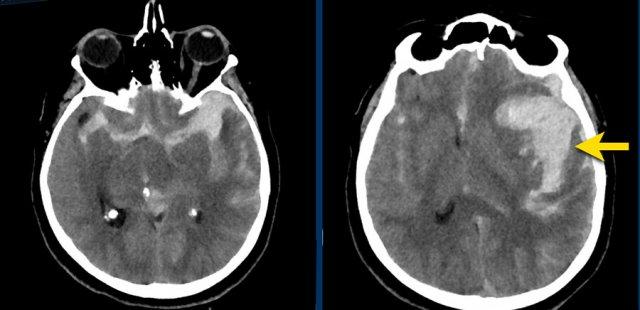

Bệnh nhân này nhập viện với não úng thủy do xuất huyết não thất (hình bên trái).

Lưu ý vùng tăng tỷ trọng rất nhỏ tại đồi thị trái, là điểm khởi phát của xuất huyết.

Theo dõi một ngày sau (hình bên phải).

Bệnh nhân được phẫu thuật đặt dẫn lưu não thất để điều trị não úng thủy.

Lưu ý đồi thị bên trái giảm tỷ trọng với ổ tăng tỷ trọng dai dẳng ở vị trí trong.